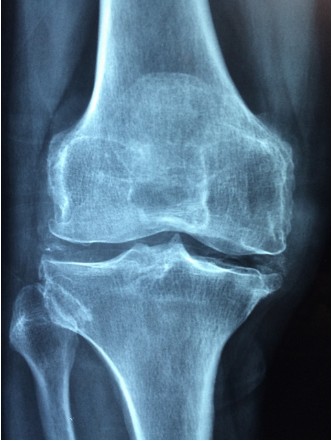

- X-선 검사: X-선 검사는 뼈의 상태를 확인할 수 있는 방법입니다. 연골의 마모 정도나 골절 여부를 알 수 있습니다.